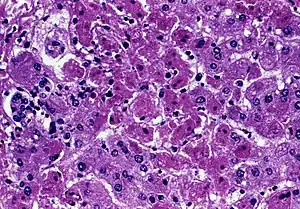

| Acute liver failure (with hepatocellular necrosis and sinusoidal bleeding) from Marburg virus, a rare cause | |